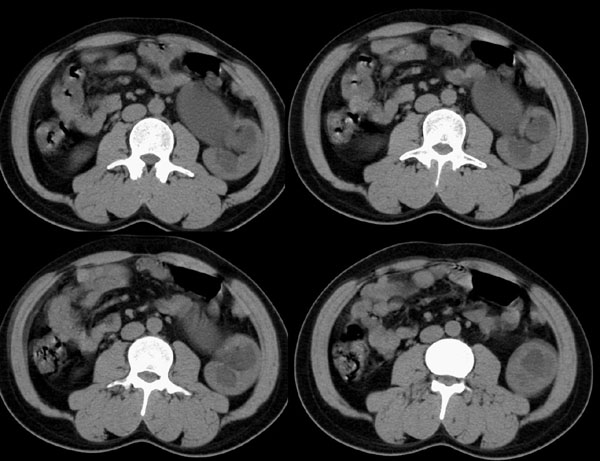

m29y平常体健,无明显不适。单位体检时发现左肾区病变。来我院作ct如下(病人不做增强):

左侧输尿管冠、矢状重建: